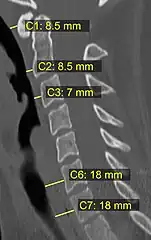

On CT scan or X-ray, a cervical fracture may be directly visualized. In addition, indirect signs of injury by the vertebral column are incongruities of the vertebral lines,[7] and/or increased thickness of the prevertebral space:[8]

X-ray of normal congruous vertebral lines